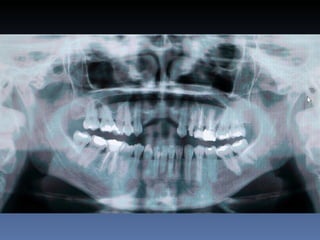

Dominga Maria silva

Idade – 53 anos

Sexo – Feminino

Raça – Caucasiana

ASA – II

Data- 23-04-2012

Diagnóstico:Desdentada parcial maxila

Plano de tratamento:      Reabilitação com 6 blocos

“onlay” provenientes de Úmero fresco-congelado

(FFB); reabertura para instalação de 6 implantes

dentários endo-ósseos e reabilitação protética fixa.

22-09-2011

20-04-2012

OPG Pré-op

Mensurações

Zona    Zona    Zona   Zona    Zona     Zona

1.6    1.3     1.1     2.1     2.3      2.6

Stage I       2,0mm   1,5mm 1,5mm 2,9mm 1,5mm         1,5mm

Pré-op (mm)

Stage I     6,5mm     7,0mm 7,1mm 5,2mm 6,7mm         7,0mm

Pós-op (mm)

Aument        4,5mm   5,5mm   5,6mm   2,3mm   5,2mm   5,5mm

o

Espessura

(mm)

Reabert       6,4mm   7,0mm   7,0mm 5,1mm     6,6mm   7,0mm

ura

Stage II

Reabsor       0,1mm   0,0mm   0,1mm   0,1mm   0,1mm   0,0mm

ção